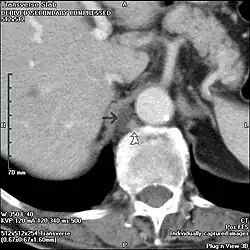

Cisterna chyli (arrow), adjacent to the azygous vein (curved arrow). Normally not visible on CT; this is an 83 male who had a CT for follow-up of gastrointestinal stromal tumour.